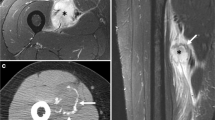

Cranial fasciitis (CF) is an uncommon benign myofibroblastic proliferation involving the soft and hard tissues of the cranium. It typically occurs in the pediatric population with a male predilection (male-to-female ratio 1.5:1). The clinical presentation is usually a rapidly expanding, painless nodule. Bone erosion may be appreciated radiographically. Histopathologic sections of CF show plump, fibroblast-like cells with pale, oval shaped nuclei and prominent nucleoli in a fibrous or myxoid background. Growth is self-limited and surgical excision is considered curative. Due to these features, CF is thought to be a variant of nodular fasciitis (NF). As with NF, CF may mimic a sarcomatous process and pose a diagnostic challenge to clinicians and pathologists alike. Erickson-Johnson et al. identified rearrangements of the ubiquitin-specific protease 6 (USP6) gene in 44 of 48 cases of NF. MYH9 was the fusion partner in 12 of these cases. To date, the molecular profile of CF has not been studied. Here we present the molecular findings in three cases of CF identified at our institution. Each case was subjected to fluorescence in-situ hybridization with appropriate negative controls. Two of three cases were positive for the USP6 gene rearrangement. The third case failed to hybridize, likely related to nucleic acid damage secondary to decalcification. Negative controls did not demonstrate the genetic rearrangement. These findings warrant further investigation of the USP6 gene rearrangement in CF, as it may prove helpful as a diagnostic adjunct in challenging cases.